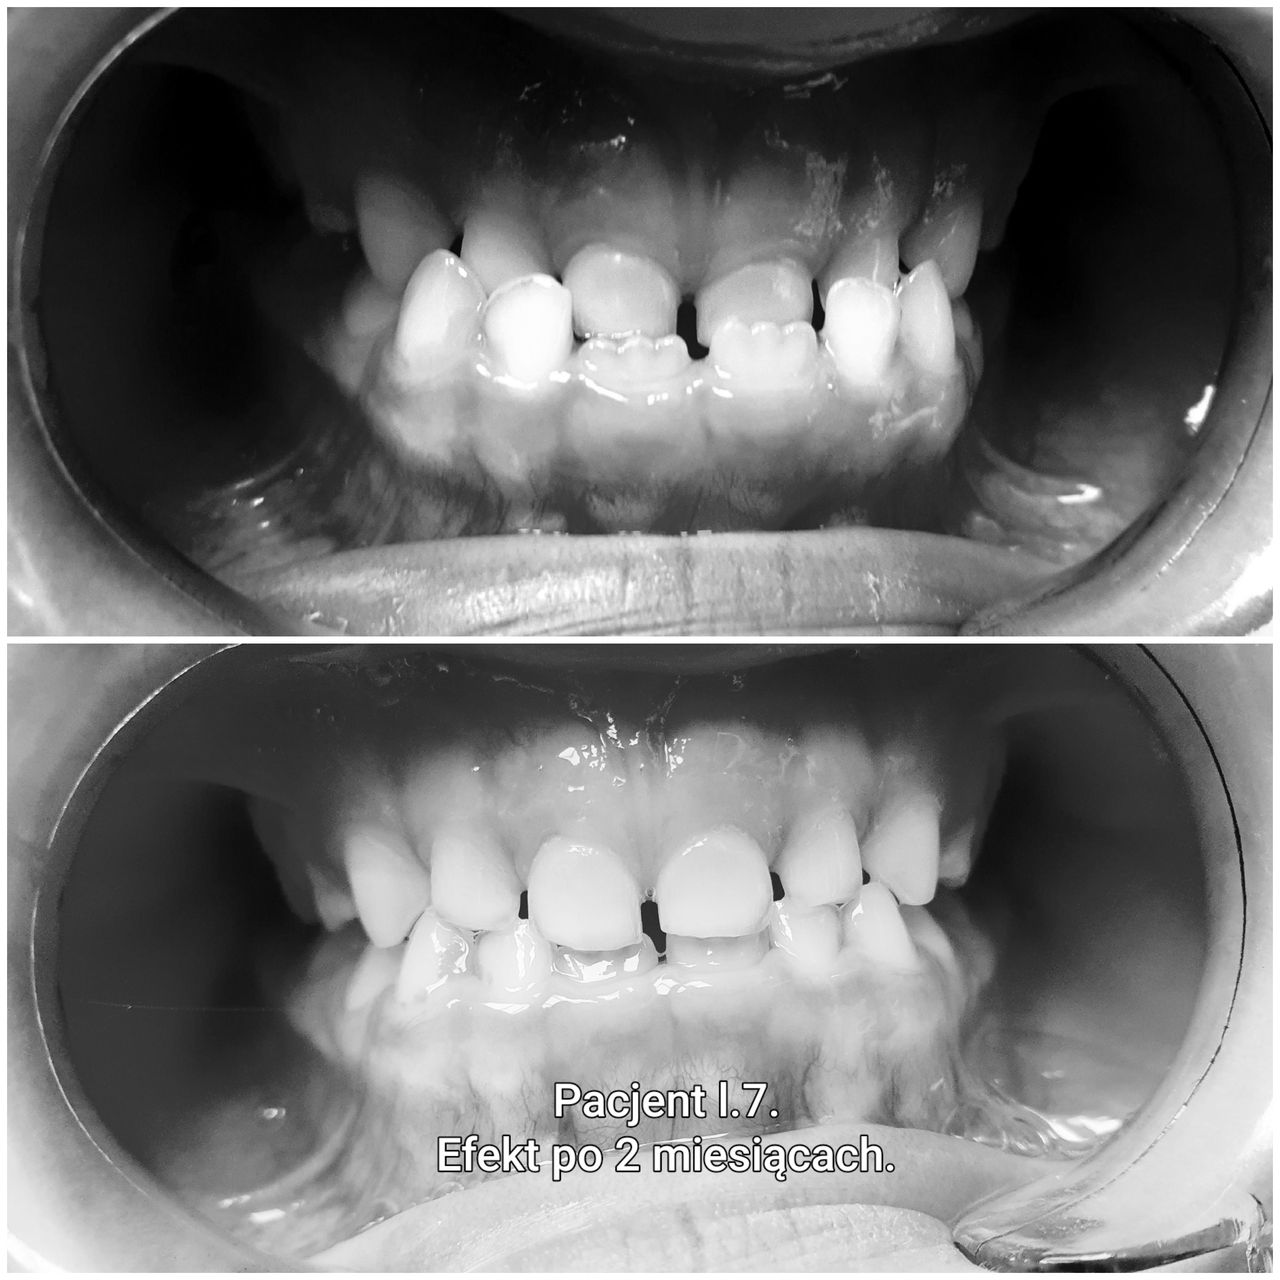

Stosowane są najczęściej u dzieci w okresie wymiany uzębienia, oraz u osób z niewielkimi wadami zgryzu . Projektowane i wykonywane są indywidualnie dla każdego pacjenta. Płytka aparatu w ulubionym kolorze, barwą ulubionego klubu piłkarskiego przypadną do gustu nawet najbardziej wymagającym małym pacjentom. Aparaty te często niesłusznie traktowane są jako gorsze niż aparaty stałe – dość powszechna jest opinia, że należy je nosić tylko w nocy, że dzieci ich nie chcą nosić oraz, że i tak na koniec konieczny będzie aparat stały. W rzeczywistości aparaty zdejmowane nie są zamiennikiem aparatów stałych, a ich uzupełnieniem. Często zaleca się ich stosowanie w pierwszym etapie leczenia, gdy nie ma jeszcze możliwości zastosowania aparatu stałego z powodu trwającej wymiany uzębienia, ale jednocześnie młody wiek pacjenta umożliwia działanie ortopedyczne np. poszerzenie łuku zębowego by w przyszłości uniknąć konieczności usuwania stałych zębów z powodu stłoczeń.